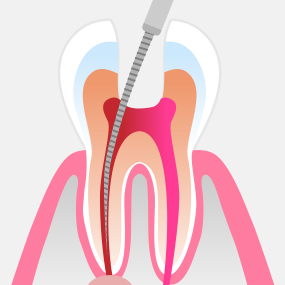

신경조직이 감염되거나 오염된 경우에는 신경치료가 필요합니다. 서울하나치과는 우수한 재료와 체계적인 치료 과정을 적용하여 안정적이고 높은 성공률의 신경치료를 제공합니다.

ROOT CANAL THERAPY

치주낭 길이 3mm 이하

치주낭 길이 3~5mm 이하

치주낭 길이 5~7mm 이하

치주낭 길이 7mm 이상